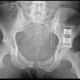

Dok, mau diskusi dong. Saya dapat pasien di IGD, habis kecelakaan motor dengan kecepatan tinggi. Pasien mengalami fraktur dan dilakukan operasi. Kemudian, pasien di rontgen kembali dan didapatkan gambar dibawah.

Apa fraktur yang terlihat pada gambar rontgen dibawah, ya dok?

Kita bisa lihat di rontgen ada hardware pada pelvic binder yang biasa digunakan untuk mengurangi volume pelvis dan menurunkan potensial ruang perdarahan. Open book pelvic fracture bersifat tidak stabil. Fraktur ini terjadi karena trauma tumpul dengan energi yang besar.

Open book pelvic fracture juga berhubungan dengan trauma tumpul dada, trauma abdominal, fraktur femur, dan trauma tulang panjang.

Pembuluh darah besar pelvis sering robek selama trauma yang mengarah pada perdarahan internal yang masif (mencapai 4 L) dan syok hipovolemik. Trauma lain yang berhubungan, yaitu uretra, bladder, vagina, uterine, rektal, dan skrotal.